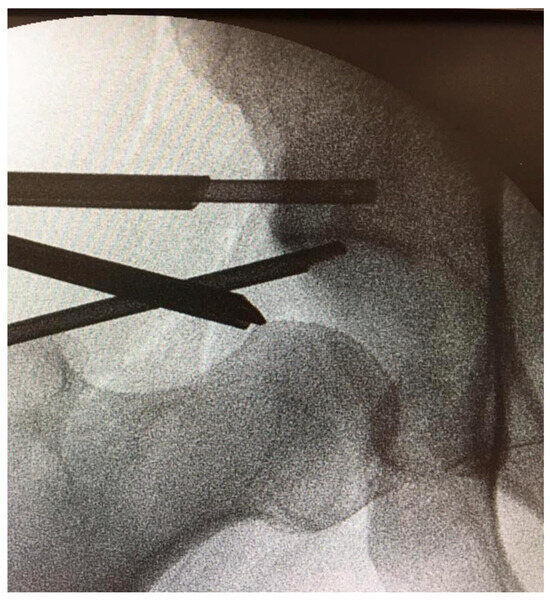

Subchondral Phosphate Injection During Hip Arthroscopy Safely Treats Acetabular Bone Marrow Lesions in Early Osteoarthritis

by Marco Minelli, Berardo Di Matteo, Vincenzo Longobardi, Alessio D’Addona, Marco Rosolani, Sebiano Pitronaci, Elizaveta Kon and Federico Della Rocca

J. Clin. Med. 2025, 14(23), 8298; https://doi.org/10.3390/jcm14238298 - 22 Nov 2025

Introduction: Arthroscopy for femoroacetabular impingement (FAI) yields inferior outcomes when subchondral edema and cystic degeneration are present. Subchondroplasty (SCP), which involves injecting osteoconductive calcium phosphate into Bone Marrow Lesions (BMLs), may enhance subchondral structural support and can be performed alongside hip arthroscopy. [...] Read more.

Introduction: Arthroscopy for femoroacetabular impingement (FAI) yields inferior outcomes when subchondral edema and cystic degeneration are present. Subchondroplasty (SCP), which involves injecting osteoconductive calcium phosphate into Bone Marrow Lesions (BMLs), may enhance subchondral structural support and can be performed alongside hip arthroscopy. Materials and Methods: This single-center retrospective study included patients who underwent SCP for acetabular BMLs during primary hip arthroscopy for FAI from March 2019 to March 2023. Clinical and radiographic outcomes were recorded at ≥2-year follow-up. Survivorship with treatment failure as the endpoint was assessed using Kaplan–Meier analysis. Results: Thirty-four patients were evaluated at a mean 3.1-year follow-up. No perioperative, early, or late complications or adverse events occurred. No bone substitute migration or intra-articular extravasation was seen. Four patients (11.8%) showed osteoarthritis progression and required conversion to total hip arthroplasty; no intraoperative issues with acetabular preparation were encountered. All clinical scores improved significantly (p < 0.001), and 82.4% returned to sport. Conclusions: SCP performed during hip arthroscopy appears safe in selected patients with early hip osteoarthritis and BMLs. Calcium phosphate injection may help restore subchondral integrity and load distribution, though the independent contribution of SCP beyond standard arthroscopic management remains uncertain. Full article

Show Figures

Figure 1